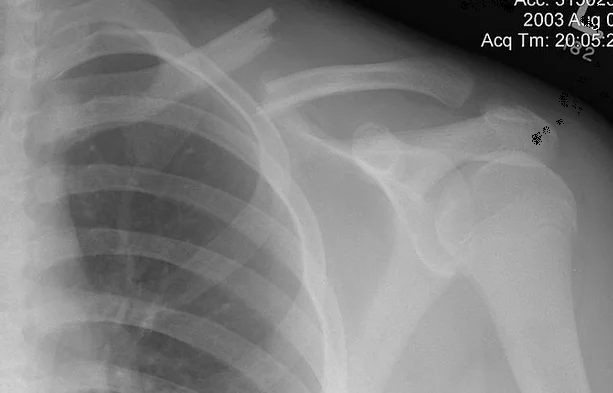

Clavicle Fracture

- Clinically;

- Pain

- Swelling

- Deformity

- Loss of motion

Clavicle Fracture: Management

- Non or minimal displaced: Typically conservative: heals well

- Figure-of-eight brace (bandage)

- Or Shoulder sling holding the elbow to overcome gravity